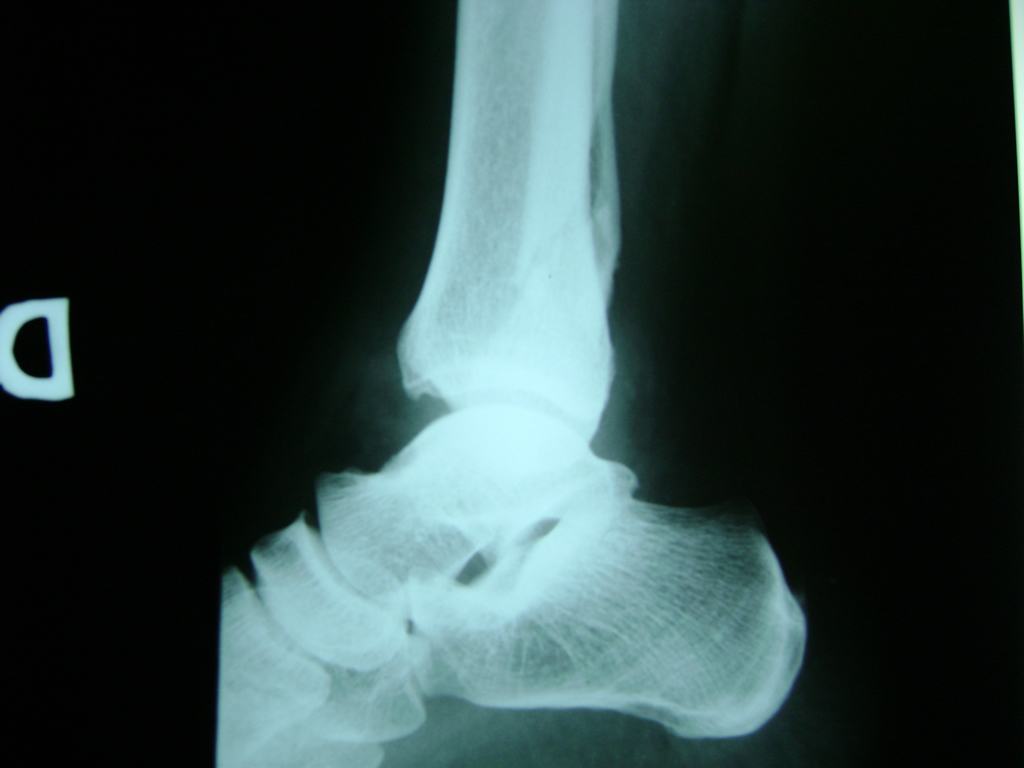

Una fractura de tobillo es la rotura de uno o más de los huesos del tobillo. Estas fracturas pueden ser:

- Parciales (el hueso está sólo parcialmente fisurado, no del todo).

- Completas (el hueso está perforado y está en 2 partes).

Algunas fracturas de tobillo pueden requerir cirugía si:

- Los extremos de los huesos están desalineados entre sí (desplazados).

- La fractura se extiende hasta la articulación del tobillo (fractura intra-articular).